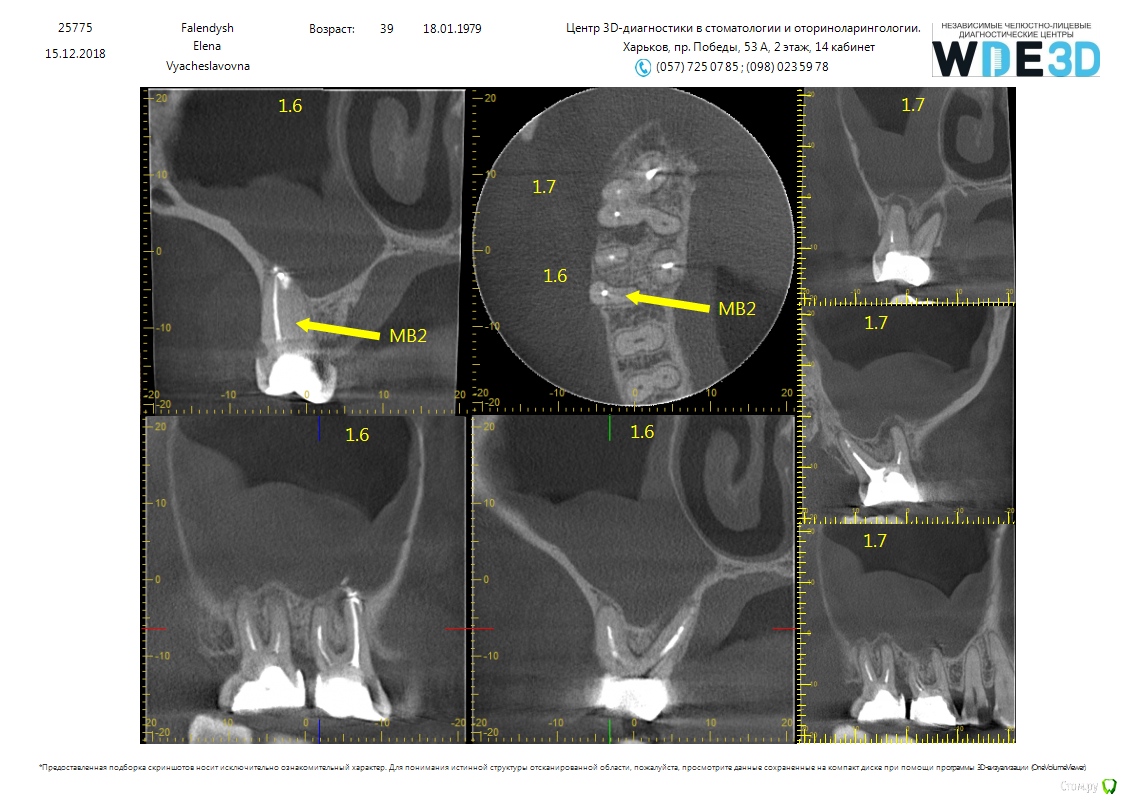

RUVIK Опубликовано 20 декабря, 2018 Поделиться Опубликовано 20 декабря, 2018 всем доброго дня. Интересует мнение профессионалов, была в нескольких клиниках. Болел 6 и 7й зуб которые ранее пломбировались (сейчас перестал, есть время принять решение), Каждый врач ставит свой диагноз, от перелечивания зубов до удаления,чистки гайморовой пазухи и наращивания кости. прикрепляю файла в разных форматах - фото Ссылка на комментарий

St. Опубликовано 20 декабря, 2018 Поделиться Опубликовано 20 декабря, 2018 Вариантов 2, диаметрально противоположных.1й Консервативный. перелечивать каналы ( есть пропущенные) и наблюдать потом 6 и 12 мес как заживает кость и уходит воспаление из гайморовой. 2й Радикальный. Если не хотите перелечивать , удаление с последующим синуслифтингом и имплантацией 2 Ссылка на комментарий

RUVIK Опубликовано 20 декабря, 2018 Автор Поделиться Опубликовано 20 декабря, 2018 Вариантов 2, диаметрально противоположных.1й Консервативный. перелечивать каналы ( есть пропущенные) и наблюдать потом 6 и 12 мес как заживает кость и уходит воспаление из гайморовой. 2й Радикальный. Если не хотите перелечивать , удаление с последующим синуслифтингом и имплантациейесть ли положительные результаты по перелечиванию (я так понимаю под микроскопом?) Ссылка на комментарий

RUVIK Опубликовано 21 декабря, 2018 Автор Поделиться Опубликовано 21 декабря, 2018 Вот прицельные снимки под микроскопом .Что скажите ,стоит ли пробовать перелечивать каналы или шансов нет? Ссылка на комментарий

RUVIK Опубликовано 21 декабря, 2018 Автор Поделиться Опубликовано 21 декабря, 2018 (изменено) Вот прицельные снимки под микроскопом .Что скажите ,стоит ли пробовать перелечивать каналы или шансов нет? Изменено 21 декабря, 2018 пользователем RUVIK Ссылка на комментарий